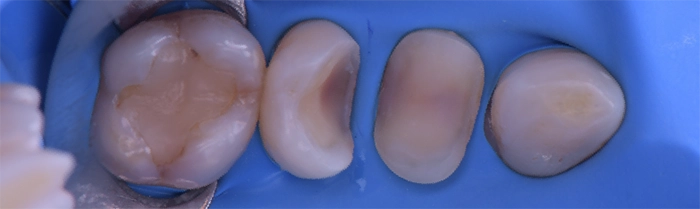

Dentisterie etsthétique

- Élément de liste #1

- Élément de liste #1

- Élément de liste #1

- Élément de liste #1